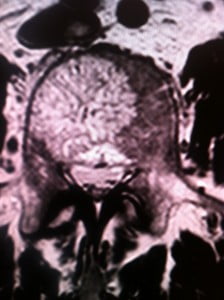

En pratique les critères établis sont simples: volume d’atteinte vertébrale supérieur à 70% de la surface porteuse corporéale, douleurs, atteinte de l’arc postérieur, signes d’agressivité en IRM (hypersignal en séquences pondérées T2 avec annulation du signal graisseux). L’atteinte des vertèbres sus jacentes à D6-D7 n’est pas un paramètre exclusif d’indication de vertebroplastie. Certaines équipes chirurgicales préconisent de consolider le corps vertébral pour une atteinte supérieure à 50% pour les vertèbres dorsales compte tenu du ratio bénéfice/risque excellent de cette intervention.

L’angiome vertébral doit être rempli dans sa quasi-totalité. Les coupes scanner successives pendant l’intervention visualisent la parfaite diffusion du ciment sur l’ensemble du corps vertébral.